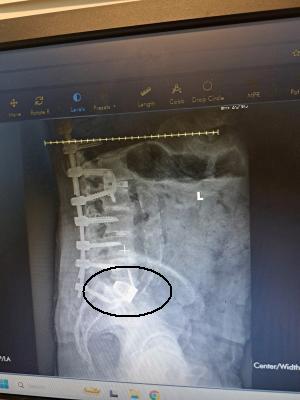

Disc Between L5 & S1 .

Beautiful .